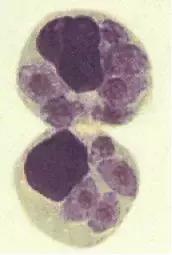

这是弓形虫假包囊

(内含速殖子)

实际上是弓形虫寄生的有核细胞